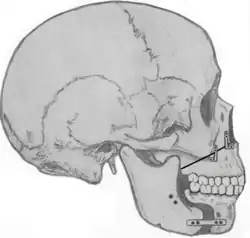

Maxillomandibular advancement (MMA) or orthognathic surgery, also sometimes called bimaxillary advancement (Bi-Max), or maxillomandibular osteotomy (MMO), is a surgical procedure or sleep surgery which moves the upper jaw (maxilla) and the lower jaw (mandible) forward. The procedure was first used to correct deformities of the facial skeleton to include malocclusion. In the late 1970s advancement of the lower jaw (mandibular advancement) was noted to improve sleepiness in three patients. Subsequently, maxillomandibular advancement was used for patients with obstructive sleep apnea.

Currently, maxillomandibular advancement surgery is often performed simultaneously with genioglossus advancement (tongue advancement). The genioglossus advancement pulls the tongue forward in a manner that decreases the amount of tongue blockage during sleep. MMA has been demonstrated to be one of the most effective surgical treatments for sleep apnea, due to its high success rate. Nonetheless, the procedure is often used after other forms of treatment have failed (nasal surgeries, tonsillectomy, uvulopalatopharyngoplasty, tongue reduction surgeries). There is a longer recovery when compared to other sleep apnea surgeries, since the bones of the face have to heal into their new position.